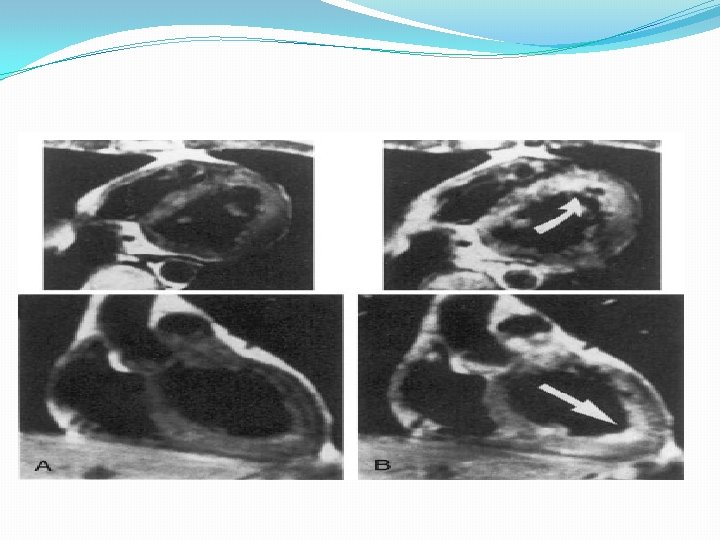

MRI �Ability to characterize tissue according to water content and changes in contrast kinetics �Detects patchy disease Extracellular contrast agents such as gadolinium. DTPA will also distribute and clear very differently in inflamed or scarred tissue compared with normal tissue, leading to changes in T 1 relaxation. Roditi et al studied 20 patients and found focal enhancement and RWMA in 18 of myocarditis patients using T 1 wtd imaging and Gd Enhancement.

T 2 -weighted imaging strategy, such as the inversion recovery sequence helps in detection of myocarditic lesions showed a sensitivity of 84% and specificity of 74% based on biopsy or natural history evidence of myocarditis. Mahrholt et al studied gadolinium-enhanced MRI-guided biopsy of the right and left ventricles in 32 patients with suspected myocarditis. Left ventricular biopsy was generally performed from the region showing the most marked contrast enhancement. Biopsy of these specific myocardial regions resulted in PPV of 71% and NPV of 100%.

CMR suggested that the lateral wall may actually be the most common location for lesion development, not the septum. Mahrholdt H, Goedecke C, Wagner A, Meinhardt G, Athanasiadis A, Vogelsberg H, Firtz P, Klingel K, Kandolf R, Sechtem U. Circulation. 2004; 109: 1250– 1258

The generally agreed CMR criteria of myocarditis include at least two (1) Regional or global myocardial signaling intensity increase in T 2 -weighted images (2) Increased global myocardial early gadolinium enhancement ratio between myocardium and skeletal muscle in gadolinium-enhanced T 1 -weighted images (3) At least one focal lesion with nonischemic regional distribution in inversion recovery prepared gadolinium-enhanced T 1 -weighted images (late gadolinium enhancement).